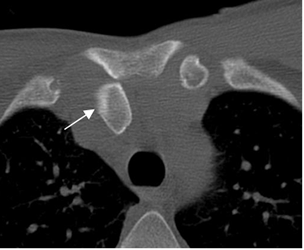

TRAUMA DE ARTICULACION ESTERNOCLAVICULAR.

Las luxaciones son de difícil detección, por lo que se necesita del TAC para hacer el diagnóstico. (1).

Las posteriores son menos frecuentes pero mas graves, por las complicaciones neurovasculares que ocasionan. (1). (Fig 56 A y B).

Fig 56A. Luxación de articulación esternoclavicular.

TAC axial. Desplazamiento posterior del tercio proximal de la clavícula, por luxación.